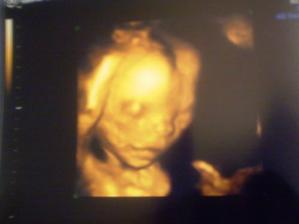

16.12. (20tt) - nam pan doktor potvrdil, ze mam v brusku DIEVCATKO a v ramci morfologie nasho babatka je vsetko v najlepsom poriadku 🙂